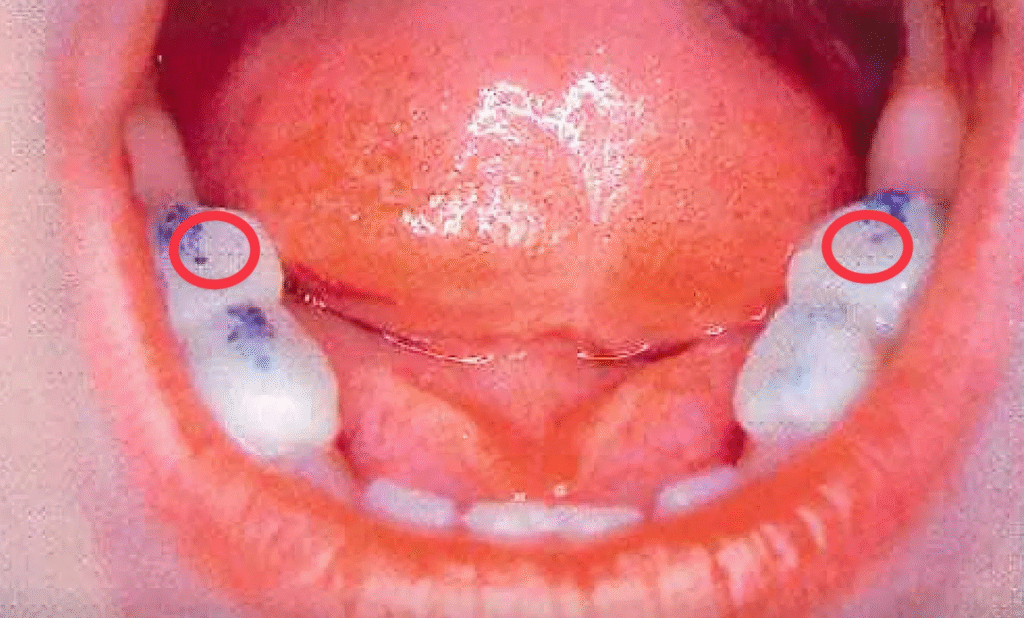

Price 獨到之處在於,他以科學的方法記錄這些差異:拍攝了成千上萬張照片,詳細測量了牙弓、臉部結構,以及整體健康指標。

- 牙弓寬廣,所有牙齒都有充裕空間;

- 牙齒天然排列整齊,幾乎不擁擠;

- 臉部發育良好,下顎骨骼強健;

- 蛀牙率極低;

那些改吃西方飲食的父母所生的孩子,臉型變窄,牙齒擁擠不齊,蛀牙也明顯增加。